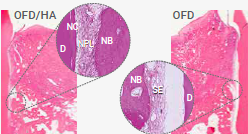

TECHNOLOGIE

Natriumhypochlorit und PERISOLV®

MODE OF ACTION

Mechanische Reinigung mit und ohne PERISOLV®

* Fördert bei der mechanischen Reinigung die Entfernung der Bakterien.